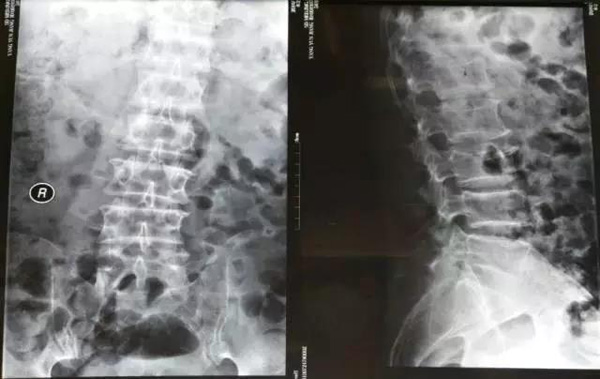

4月前无明显诱因出现腰痛伴双下肢无力,无法站立行走并出现大小便困难,大便8天未解,服用通便药物无效。当地医院腰椎MR检查显示椎管内分叶状占位,性质待定。遂来我院就诊,以“腰椎间盘突出症”收住疼痛科,行经皮腰椎间孔镜髓核摘除术。

手术经过:轮椅推入手术室,取府卧位,腹下垫软枕,C形臂X线透视确定L4/5左侧小关节内侧缘为穿刺进针点并标记,洗手穿手术衣,常规消毒,铺治疗巾,给病人保护套,铺大洞巾,局麻(2%利多卡因10ml,20ml生理盐水)皮丘5ml,从穿刺点进针后,C臂调整针正位位于L4/5左侧小关节内侧缘,侧位位于L4/5椎间盘内,推注1ml造影剂,透视确认位置,放置导丝,手术刀片切皮,六级扩张管逐级扩张后放工作套管,透视确认位置正确,连接各种线路(镜头视频线、光源线、水管、手柄电极)并固定,调整镜头焦距,测试电极强度,镜子确认位置,发现硬膜囊受压,初步清理蓝染的髓核,逐渐分辨神经要、硬膜囊及后纵韧带,各个方向清理突出变性髓核、射频电极止血。解除压迫以后,硬膜囊、神经根颜色由苍白变为红润,博动良好,以双极射频消融、止血、修整纤维环裂口,以使皱缩成形,电转磨除部分增生的上关节突,扩大椎间孔。退出工作套管缝合切口,无菌敷贴贴穿刺点,术中患者生命体征平稳,术毕患者腰背部疼痛及双下肢无力消失。